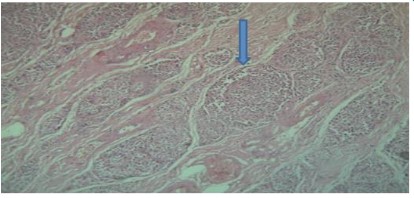

The gross cystic mass measures 10 x 7 x 5 cms, external surface was bosselated irregular with congestion, the normal pancreatic tissue was pushed to the periphery. The cyst was sectioned to reveal tan and red variegated cystic and solid cut surfaces. Microscopic examination demonstrated cystic wall lined by glycogen rich clear cells arranged in a single cuboidal layer without mucin. The Linning epithelial cells demonstrate high grade of dysplasia and foci of microinvasive adenocarcinoma. Perineural and lymphovascular invasion were not identfied. Immunohistochemistry was performed for further confirmation which showed CK-7, CK- 19, CA19.9 positive while CK-20, CDX-2, CEA were negative thus diagnosis of serous cystadenocarcinoma was confirmed.

Figure 4 & 5: Pancreatic cystic adenocarcinoma with high grade dysplasia in lining epithelium and foci of microinvasion.